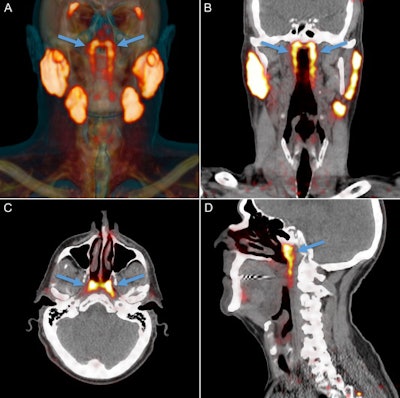

PSMA-PET projected as orange signal on reference CT. The parotid, submandibular, and sublingual salivary glands abundantly express PSMA. An unknown structure in the nasopharynx showed similar imaging characteristics (arrows). Location and extent of the tubarial glands in a random patient. Shown are coronal (B), axial (C), and sagittal (D) slices at the level of the torus tubarius of PSMA-PET projected as yellow signal on grayscale CT. The glandular structure is visible as PSMA-positive tissue (arrows). The coronal slices also show some parts of the parotid and submandibular glands, which demonstrate similar imaging characteristics. All images courtesy of Valstar et al. Licensed under CC BY-NC 4.0."To our knowledge, this is the first description of paired macroscopic (sero)mucous gland locations in the human posterolateral nasopharyngeal wall, and an indication of their clinical relevance in [radiation therapy] for HNC," wrote the group, led by Dr. Matthijs Valstar from the department of head and neck oncology and surgery at the Netherlands Cancer Institute (Radiotherapy & Oncology, 22 September 2020).

PSMA-PET/CT can visualize salivary glands with high sensitivity and specificity, Valstar and colleagues wrote. This allowed the researchers to observe an unknown bilateral structure posterior in the nasopharynx, with radiopharmaceutical uptake much like that of the known major parotid, submandibular, and sublingual salivary glands.

All 100 patients with prostate or urethral gland cancer demonstrated a divided bilateral PSMA-positive area with an average length of 4 cm. Examining the glands and 3D reconstruction confirmed the presence of PSMA-expressing, predominantly mucous glands with multiple draining ducts. They were found predominantly near the torus tubarius, according to the authors.